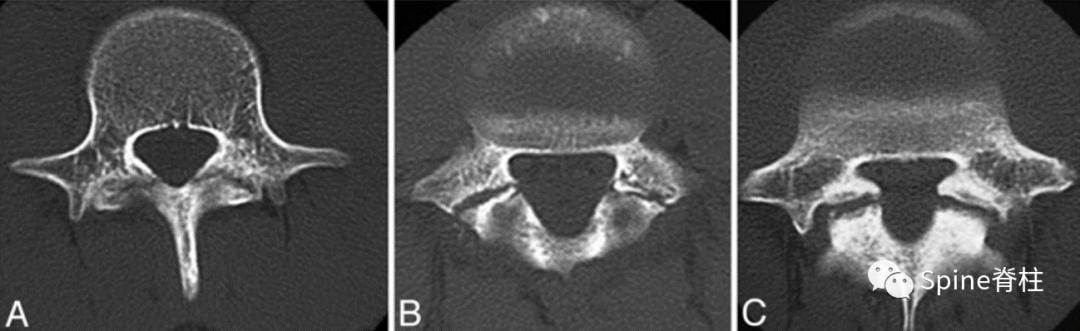

峡部裂的CT分型 :A=早期(线性骨折),B=进展期(明显的骨间隙),C=终末期(假关节形成)